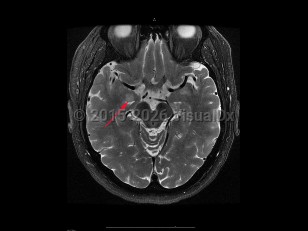

Encephalitis refers to direct inflammation of brain tissue. Patients present with abnormalities in brain function, altered mental status, personality changes, behavioral changes, sensory deficits, motor deficits, and speech disorders. Other manifestations include hemiparesis, flaccid paralysis, seizures, and paresthesias.

To distinguish encephalitis from other causes of encephalopathy, core components of the presentation of encephalitis include the presence of fever (within 72 hours before or after presentation), cerebrospinal fluid (CSF) pleocytosis (≥ 5 /mm3), or MRI or electroencephalogram (EEG) changes consistent with encephalitis.

Encephalitis is often secondary to a virus but may be caused by bacteria, fungi, or toxins. Three of the most common etiologic agents for acute encephalitis are viral including herpes simplex virus (HSV), varicella-zoster virus (VZV), and enterovirus. Alternatively, encephalitis can be caused by autoimmune conditions (anti-NMDAR encephalitis, lupus cerebritis) or inflammatory or paraneoplastic conditions, or be a consequence of stem cell transplant. Patients with encephalitis may also have concomitant meningitis (meningoencephalitis).